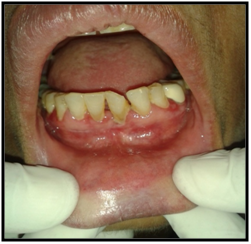

On intraoral examination, diffuse lesions in the form of erythematous areas were seen interspersed within white keratotic areas present all over the facial aspect of gingiva (Figure 2) and more posteriorly on the buccal mucosae bilaterally (Figure 3). Left buccal mucosa showed a white erythematous patch measuring approximately 2x2.5cms extending anteroposteriorly from the area adjacent to mandibular first molar to the retro molar pad area and superior inferiorly from the line of occlusion to the upper and lower lingual vestibule. White radiating striae (wickhamstriae) were present with an interspersed erythematous patch. Right buccal mucosa showed a more extensive lesion measuring approximately 2.5x3cms extending anteroposteriorly from the region adjacent to mandibular canine to the retromolar pad area and superioinferiorly from the upper gingiva buccal sulcus to the lower gingivobuccal sulcus and the alveolar mucosa. Borders of the lesion appear irregular and ill defined. On palpation, the lesions appeared to be tender. The surface of the lesions were rough and non scrapable with no induration noted.

Figure 3 The lesion on the facial gingiva.